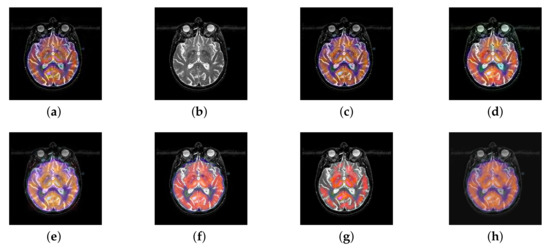

In this section, there are four multi-modal image sets and each set is consist of MRI image and SPECT image that are corresponding to the sanme location slice of the brain as shown in Figure 7. Among them, Figure 7e,f are captured from patients who have suffered a subacute stroke. Figure 7a–d,g,h are captured from patients who have brain tumor. The fused images with different fusion methods based on DTCWT, NSCT, GFF, LPSR, IGM, DDcGAN, FusionCNN, and the proposed methods are shown in Figure 8, Figure 9, Figure 10 and Figure 11. It can be seen that the fused images obtained by LPSR and FusionCNN algorithm have serious color distortion. Based on DTCWT and NSCT algorithm, the fusion image structure information is not obvious. The fused images obtained by GFF and IGM algorithm contain almost no color information, which is not conducive for doctors to make correct diagnosis. The image obtained by the DDcGAN algorithm saves the color information in the SPECT to a great extent; however, the brightness of the fused image is too large, which causes the image to have no sense of hierarchy and the contrast to decrease. By comparing with other algorithms, we find that our algorithm has good color retention effect, clear structure information, moderate brightness, and no artifacts.

Figure 8.

Fused medical images obtained by different algorithms (Figure 7a,b): (a) dual tree complex wavelet transform (DTCWT), (b) guided filtering fusion (GFF), (c) non-subsampled contourlet transform (NSCT), (d) Laplacian pyramid sparse representation (LPSR), (e) internal generative mechanism (IGM), (f) Fusion convolutional neural network based (FusionCNN), (g) dual-discriminator conditional generative adversarial network based (DDcGAN), and (h) FusionNet.

Figure 9.

Fused medical images obtained by different algorithms (Figure 7c,d): (a) DTCWT, (b) GFF, (c) NSCT, (d) LPSR, (e) IGM, (f) FusionCNN, (g) DDcGAN, and (h) FusionNet.

Figure 10.

Fused medical images obtained by different algorithms (Figure 7e,f): (a) DTCWT, (b) GFF, (c) NSCT, (d) LPSR, (e) IGM, (f) FusionCNN, (g) DDcGAN, and (h) FusionNet.

Figure 11.

Fused medical images obtained by different algorithms (Figure 7g,h): (a) DTCWT, (b) GFF, (c) NSCT, (d) LPSR, (e) IGM, (f) FusionCNN, (g) DDcGAN, and (h) FusionNet.

From Figure 12 and Figure 13, we find that algorithm obtains the greatest preference, indicating that FusionNet can get better fusion results from the subjective aspect. The objective evaluation metrics of fused images of all methods in the MRI-SPECT image fusion are shown in Figure 14, Figure 15, Figure 16, Figure 17, Figure 18, Figure 19, Figure 20, Figure 21, Figure 22 and Figure 23. Our FusionNet performs well on SSIM, , , and VIF in MRI and SPECT fusion images. In terms of EN, CE, AG, and FMI, our algorithm is slightly inferior to DDcGAN, IGM, GFF, and FusionCNN. As for the remaining two indicators, our algorithm is similar to other algorithms. Subjective evaluation and objective evaluation are inconsistent sometimes; however, in medical diagnosis, objective evaluation cannot be a complete basis for diagnosis, while subjective evaluation is often more comprehensive. However, the fusion images got by FusionNet have achieved good results in subjective and objective evaluation.